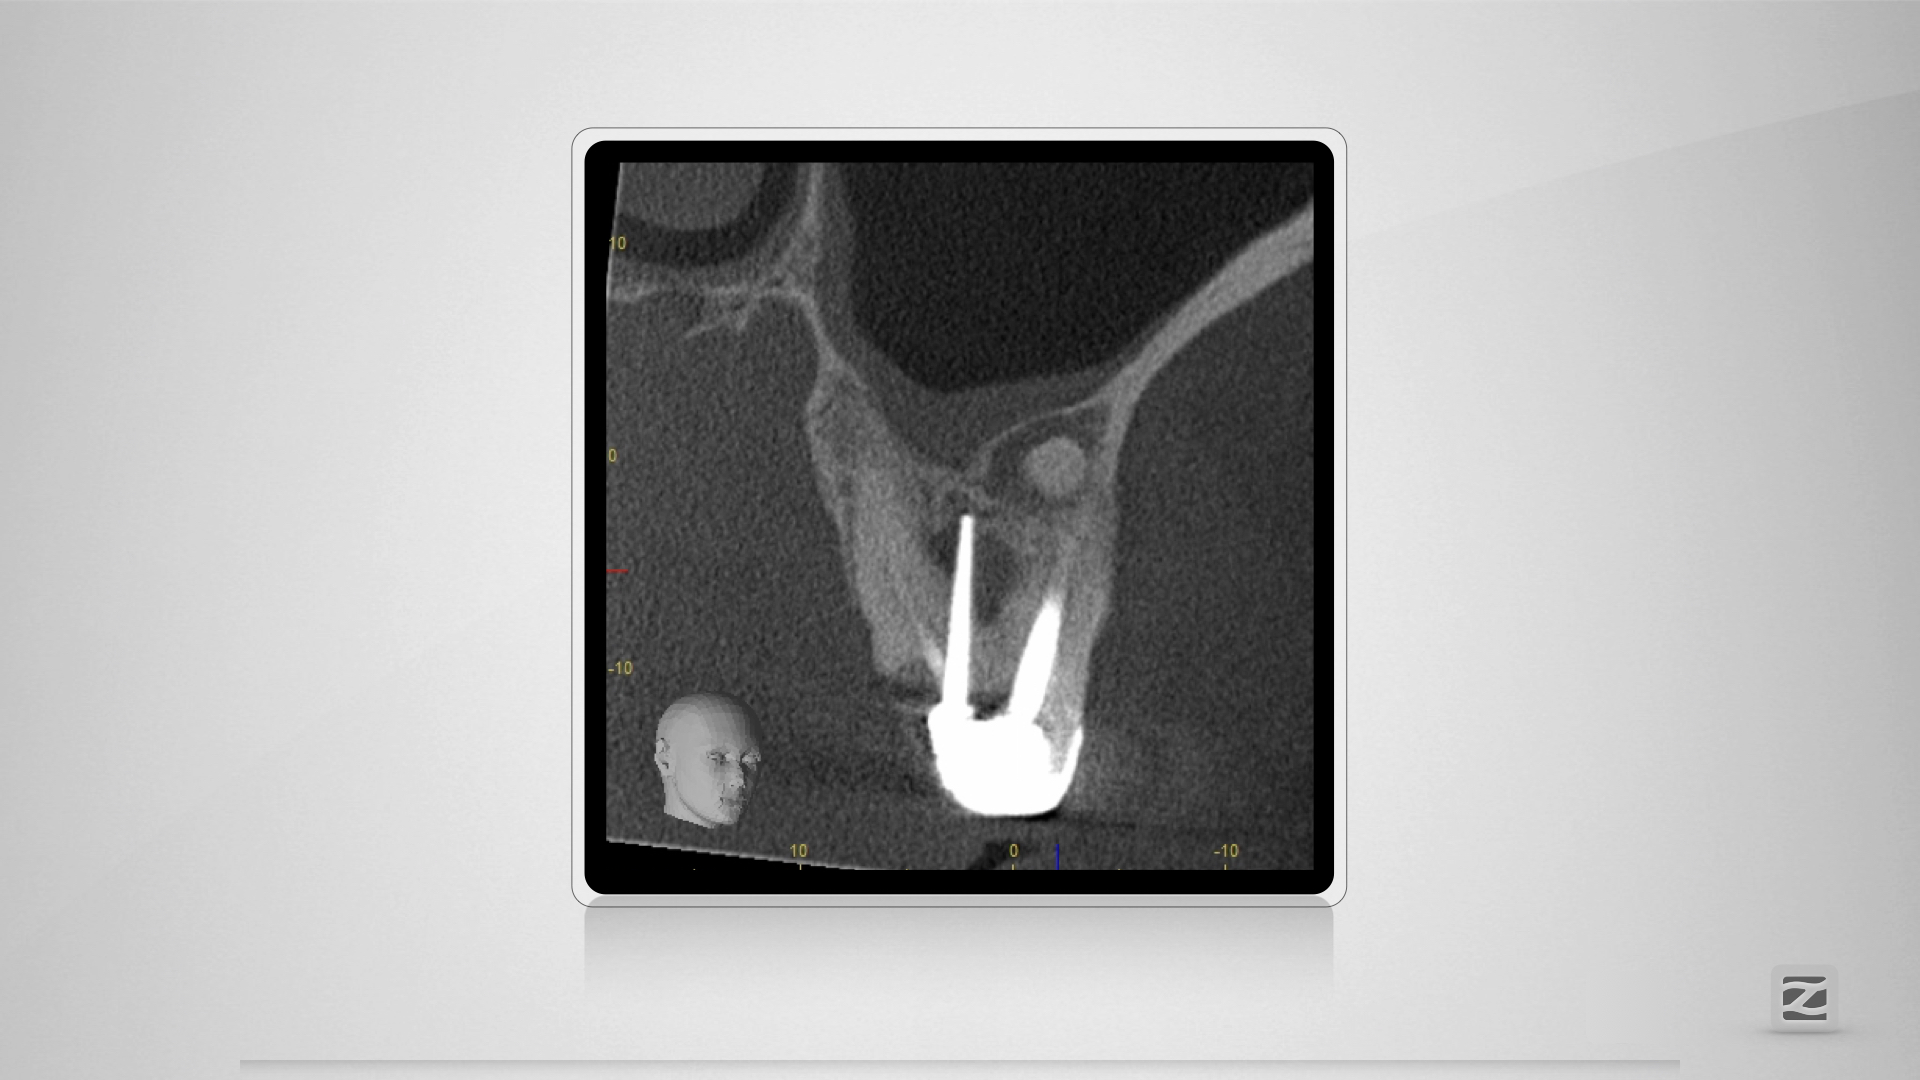

26D.005

Taktikbesprechung